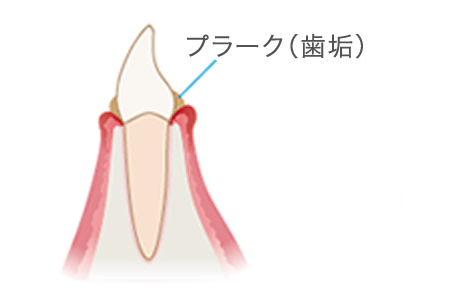

歯周病とは細菌によって感染するお口の病気です。一昔前まで歯槽膿漏とも呼ばれていました。お口の中には、常に300〜500種類の細菌がいます。これらの菌は普段何も悪いことはしませんが、食事などの食べかす(歯垢/プラーク)が溜まるとそこに菌が集まり、その歯垢を巣として何億もの歯周病菌が住み着いて歯周病を引き起こします。

歯茎の溝(歯周ポケット)に隠れたプラーク(細菌の塊)によって発症します。歯垢は歯ブラシやうがいである程度落とすことはできますが、全て取り除くことは不可能と言われていおり、磨き残された歯垢はやがて歯石となってしまいます。歯石には小さな穴や隙間があり、そこが新たな細菌の住処となります。こうして細菌はどんどんお口の中で繁殖し、歯周病は悪化していきます。

歯肉炎〜軽度の歯周炎

歯と歯ぐきの間にプラークがたまって歯ぐきが腫れ、出血しやすくなっています。歯を支える骨にはまだあまり影響がありません。